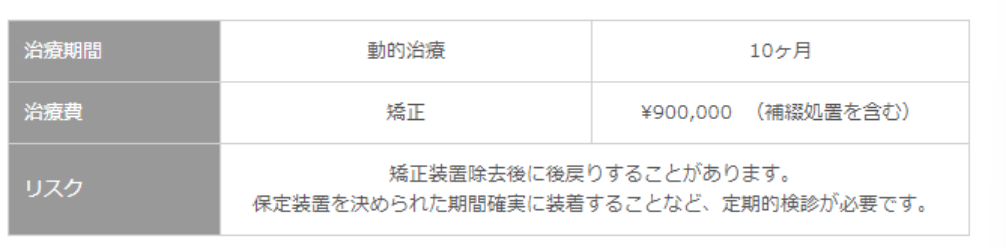

治療期間・治療費・リスク

治療後のリコール時におけるリスクマネジメント

- 矯正装置除去後に後戻りすることがあるので、保定装置を決められた期間確実に装着してください。

- リコールによる継続定期検診が必要となります。